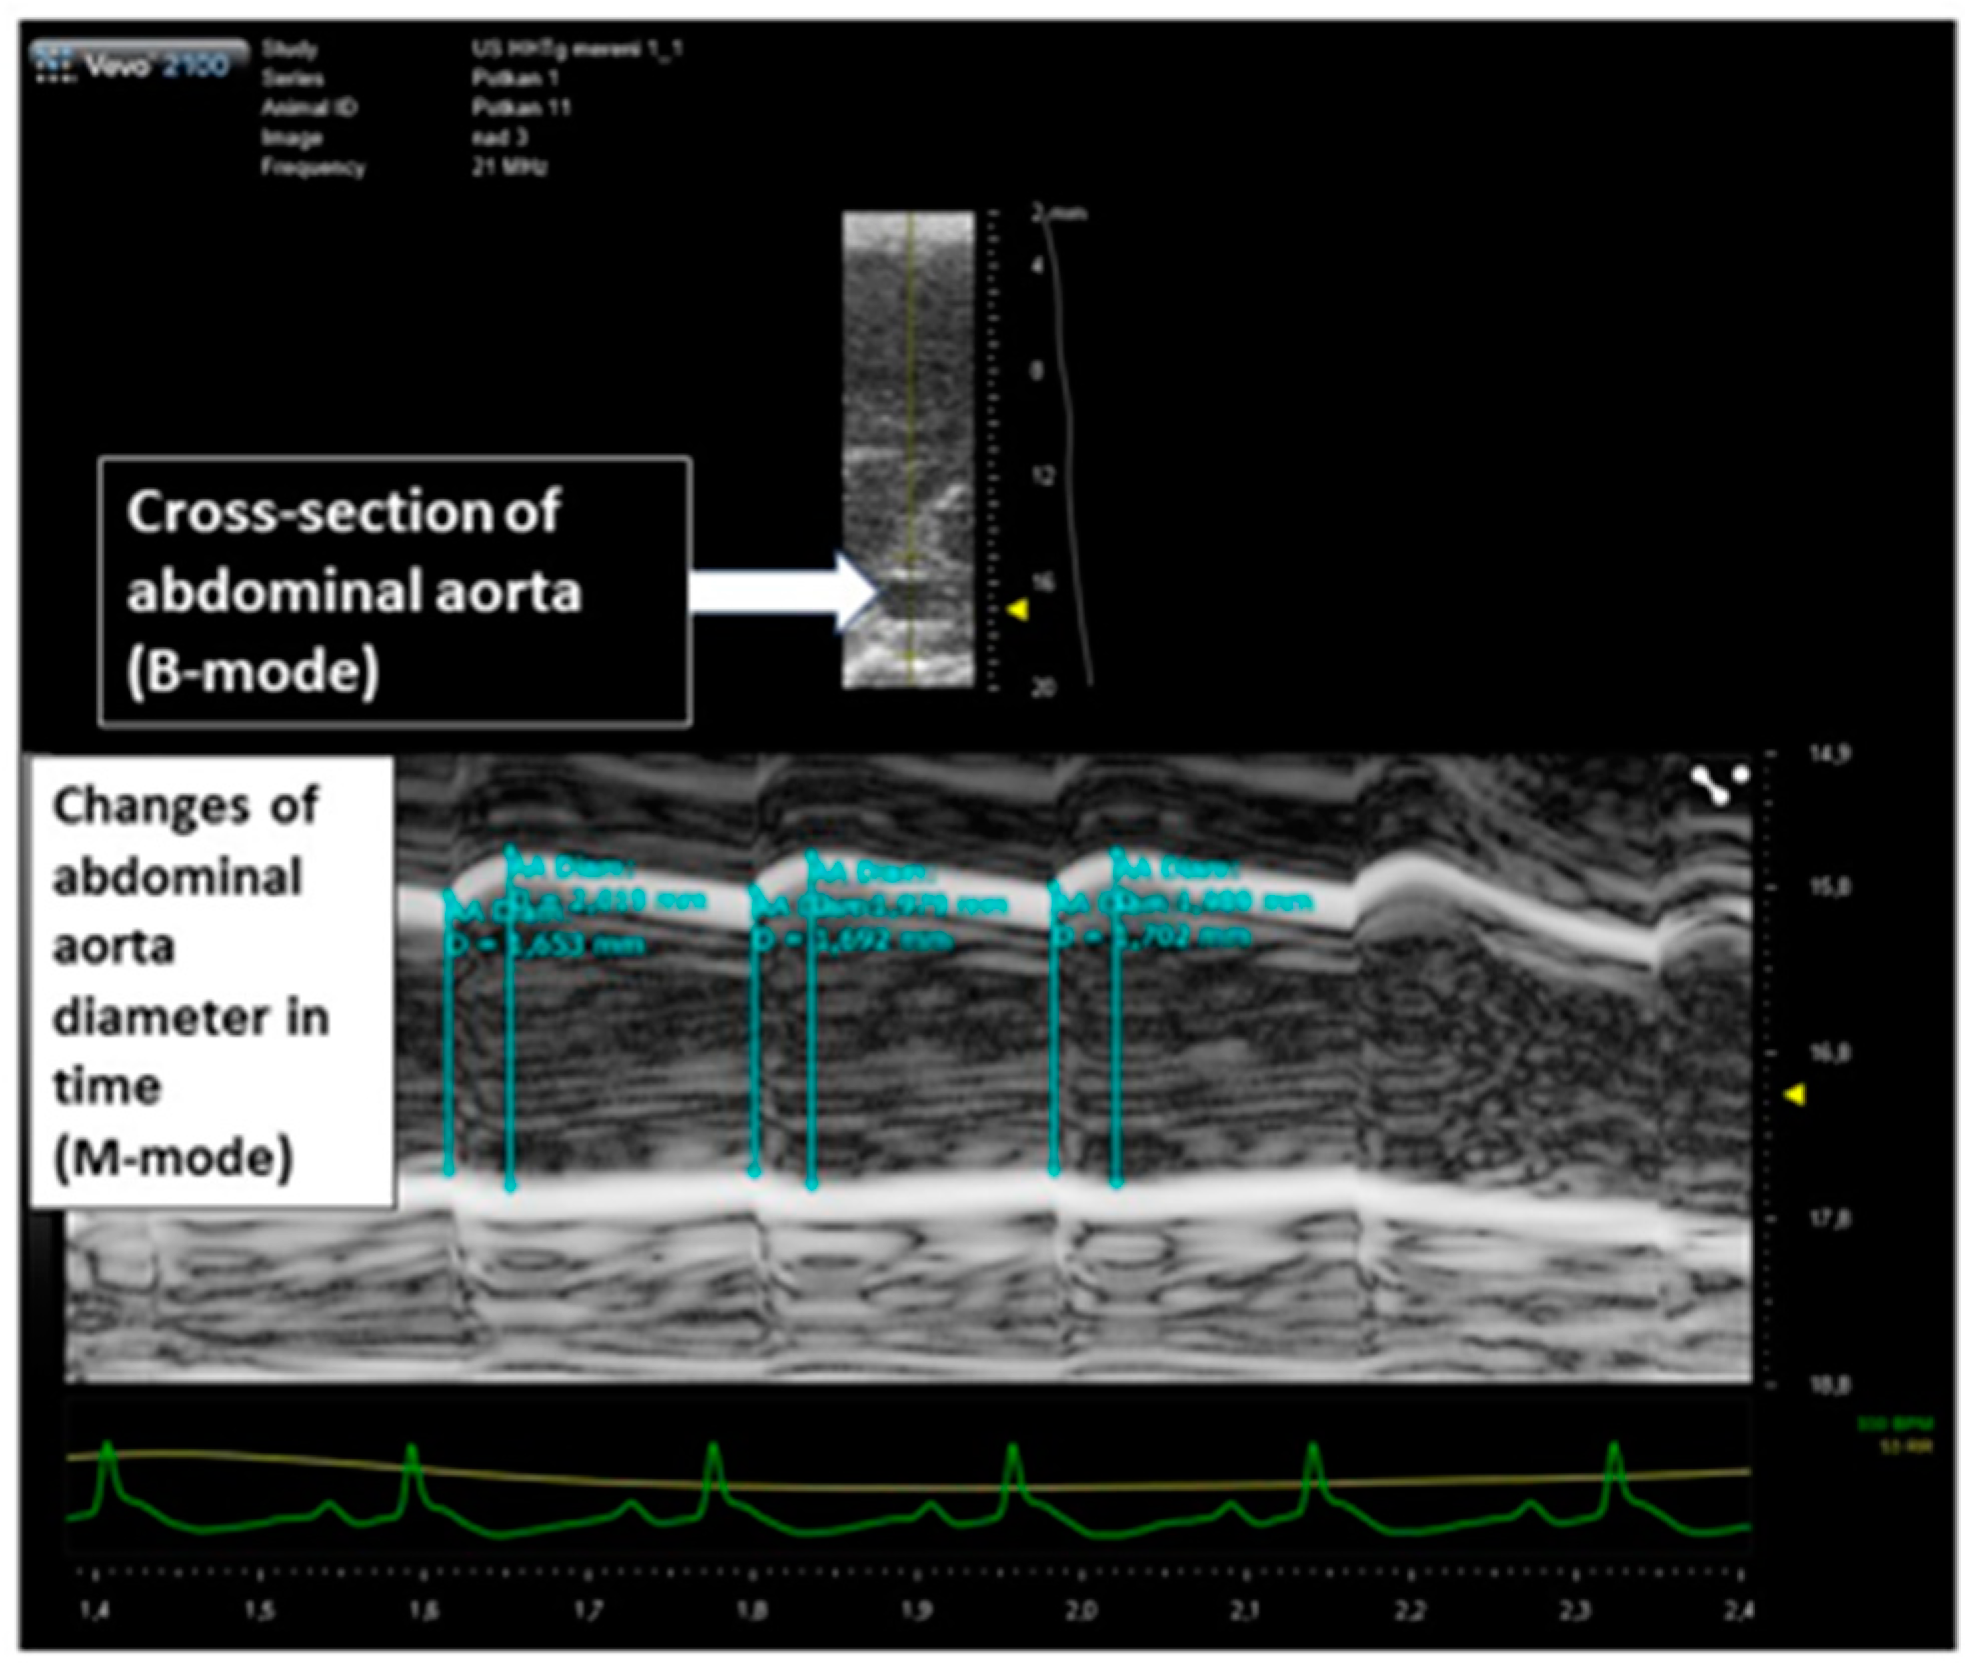

2.1. Changes of Cardiovascular Parameters after Ovariectomy and Estradiol Substitution

4.2. Ultrasound Studies

- Knipp, B.S.; Ailawadi, G.; Sullivan, V.V.; Roelofs, K.J.; Henke, P.K.; Stanley, J.C.; Upchurch, G.R., Jr. Ultrasound meas-urement of aortic diameters in rodent models of aneurysm disease. J. Surg. Res. 2003, 112, 97–101. [Google Scholar] [CrossRef]